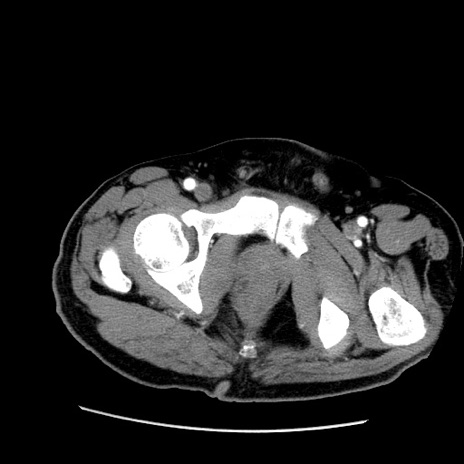

冠状断像

【症例】50歳代男性

【主訴】腹痛

【現病歴】AVMからの被殻出血のため回復期リハ病棟入院中。 本日午後3時頃急に下腹部痛が出現した。

【既往歴】AVM、被殻出血、虫垂炎、高血圧

【身体所見】意識晴明、左半身不全麻痺、会話の理解は良好、36.5°C、腹部:膨隆、全体に板状硬、下腹部正中に圧痛点あり、反跳痛-、筋性防御不明、右下腹部にope scar

【データ】WBC 9400、CRP 0.06